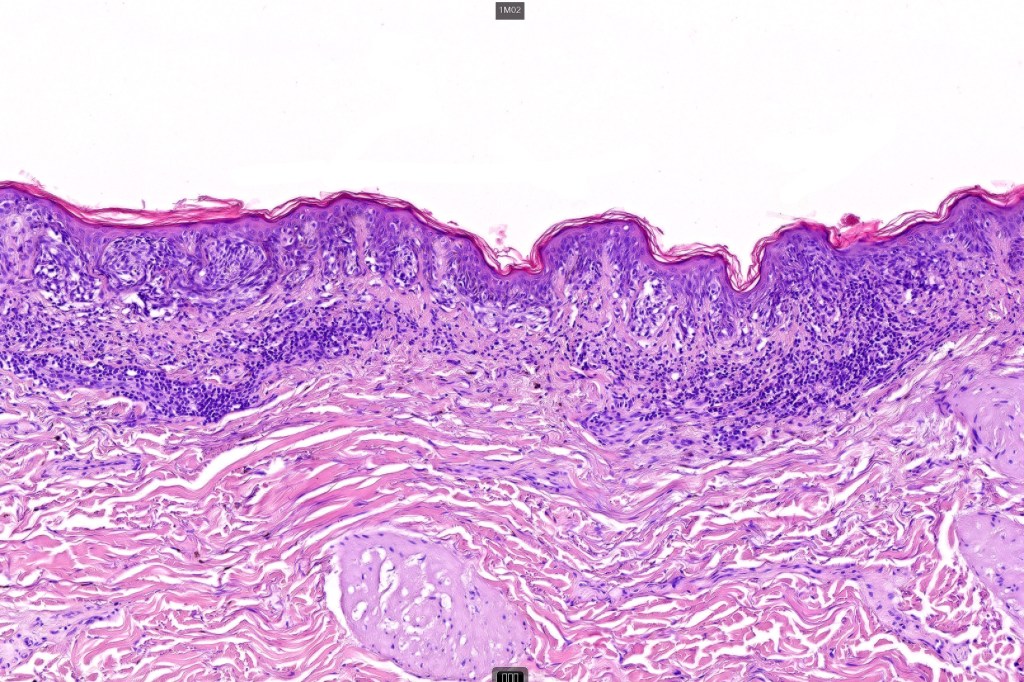

•+/- Lentigo maligna (some examples are devoid of a junctional component)

•Lymphoid aggregates*